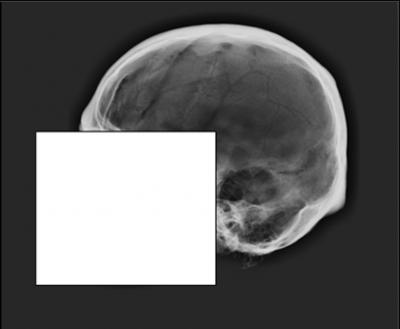

At issue is the "cranial vault outline," not the "face" of the skull. The cranial vault outline is the profile of the skull when viewed from the side, running from just above the bridge of the nose to the point where the skull and neck meet.

For the study, the researchers surveyed 106 members of the American Academy of Forensic Sciences. Survey participants were asked to evaluate 14 antemortem X-rays and five postmortem X-rays. Participants were then asked to match the 5 postmortem X-rays with the appropriate antemortem X-ray, effectively establishing a positive ID.

But the researchers found that only 47 percent of the participants made accurate identifications on all five skulls. Participants who have Ph.D.s did slightly better, with 56 percent of them getting all five correct. (The test has been made available at http://web.ncsu.edu/abstract/science/wms-skull-xray-test/ so that anyone can take it.)